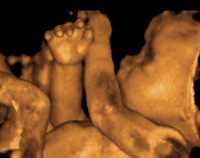

EmbarazoDurante el embarazo y las sucesivas ecografías que nos hacemos, uno de los recuerdos que permanecen en nuestra memoria son las medidas del feto, el peso y algún dato más. No obstante, la longitud del futuro bebé es uno de los datos de más...